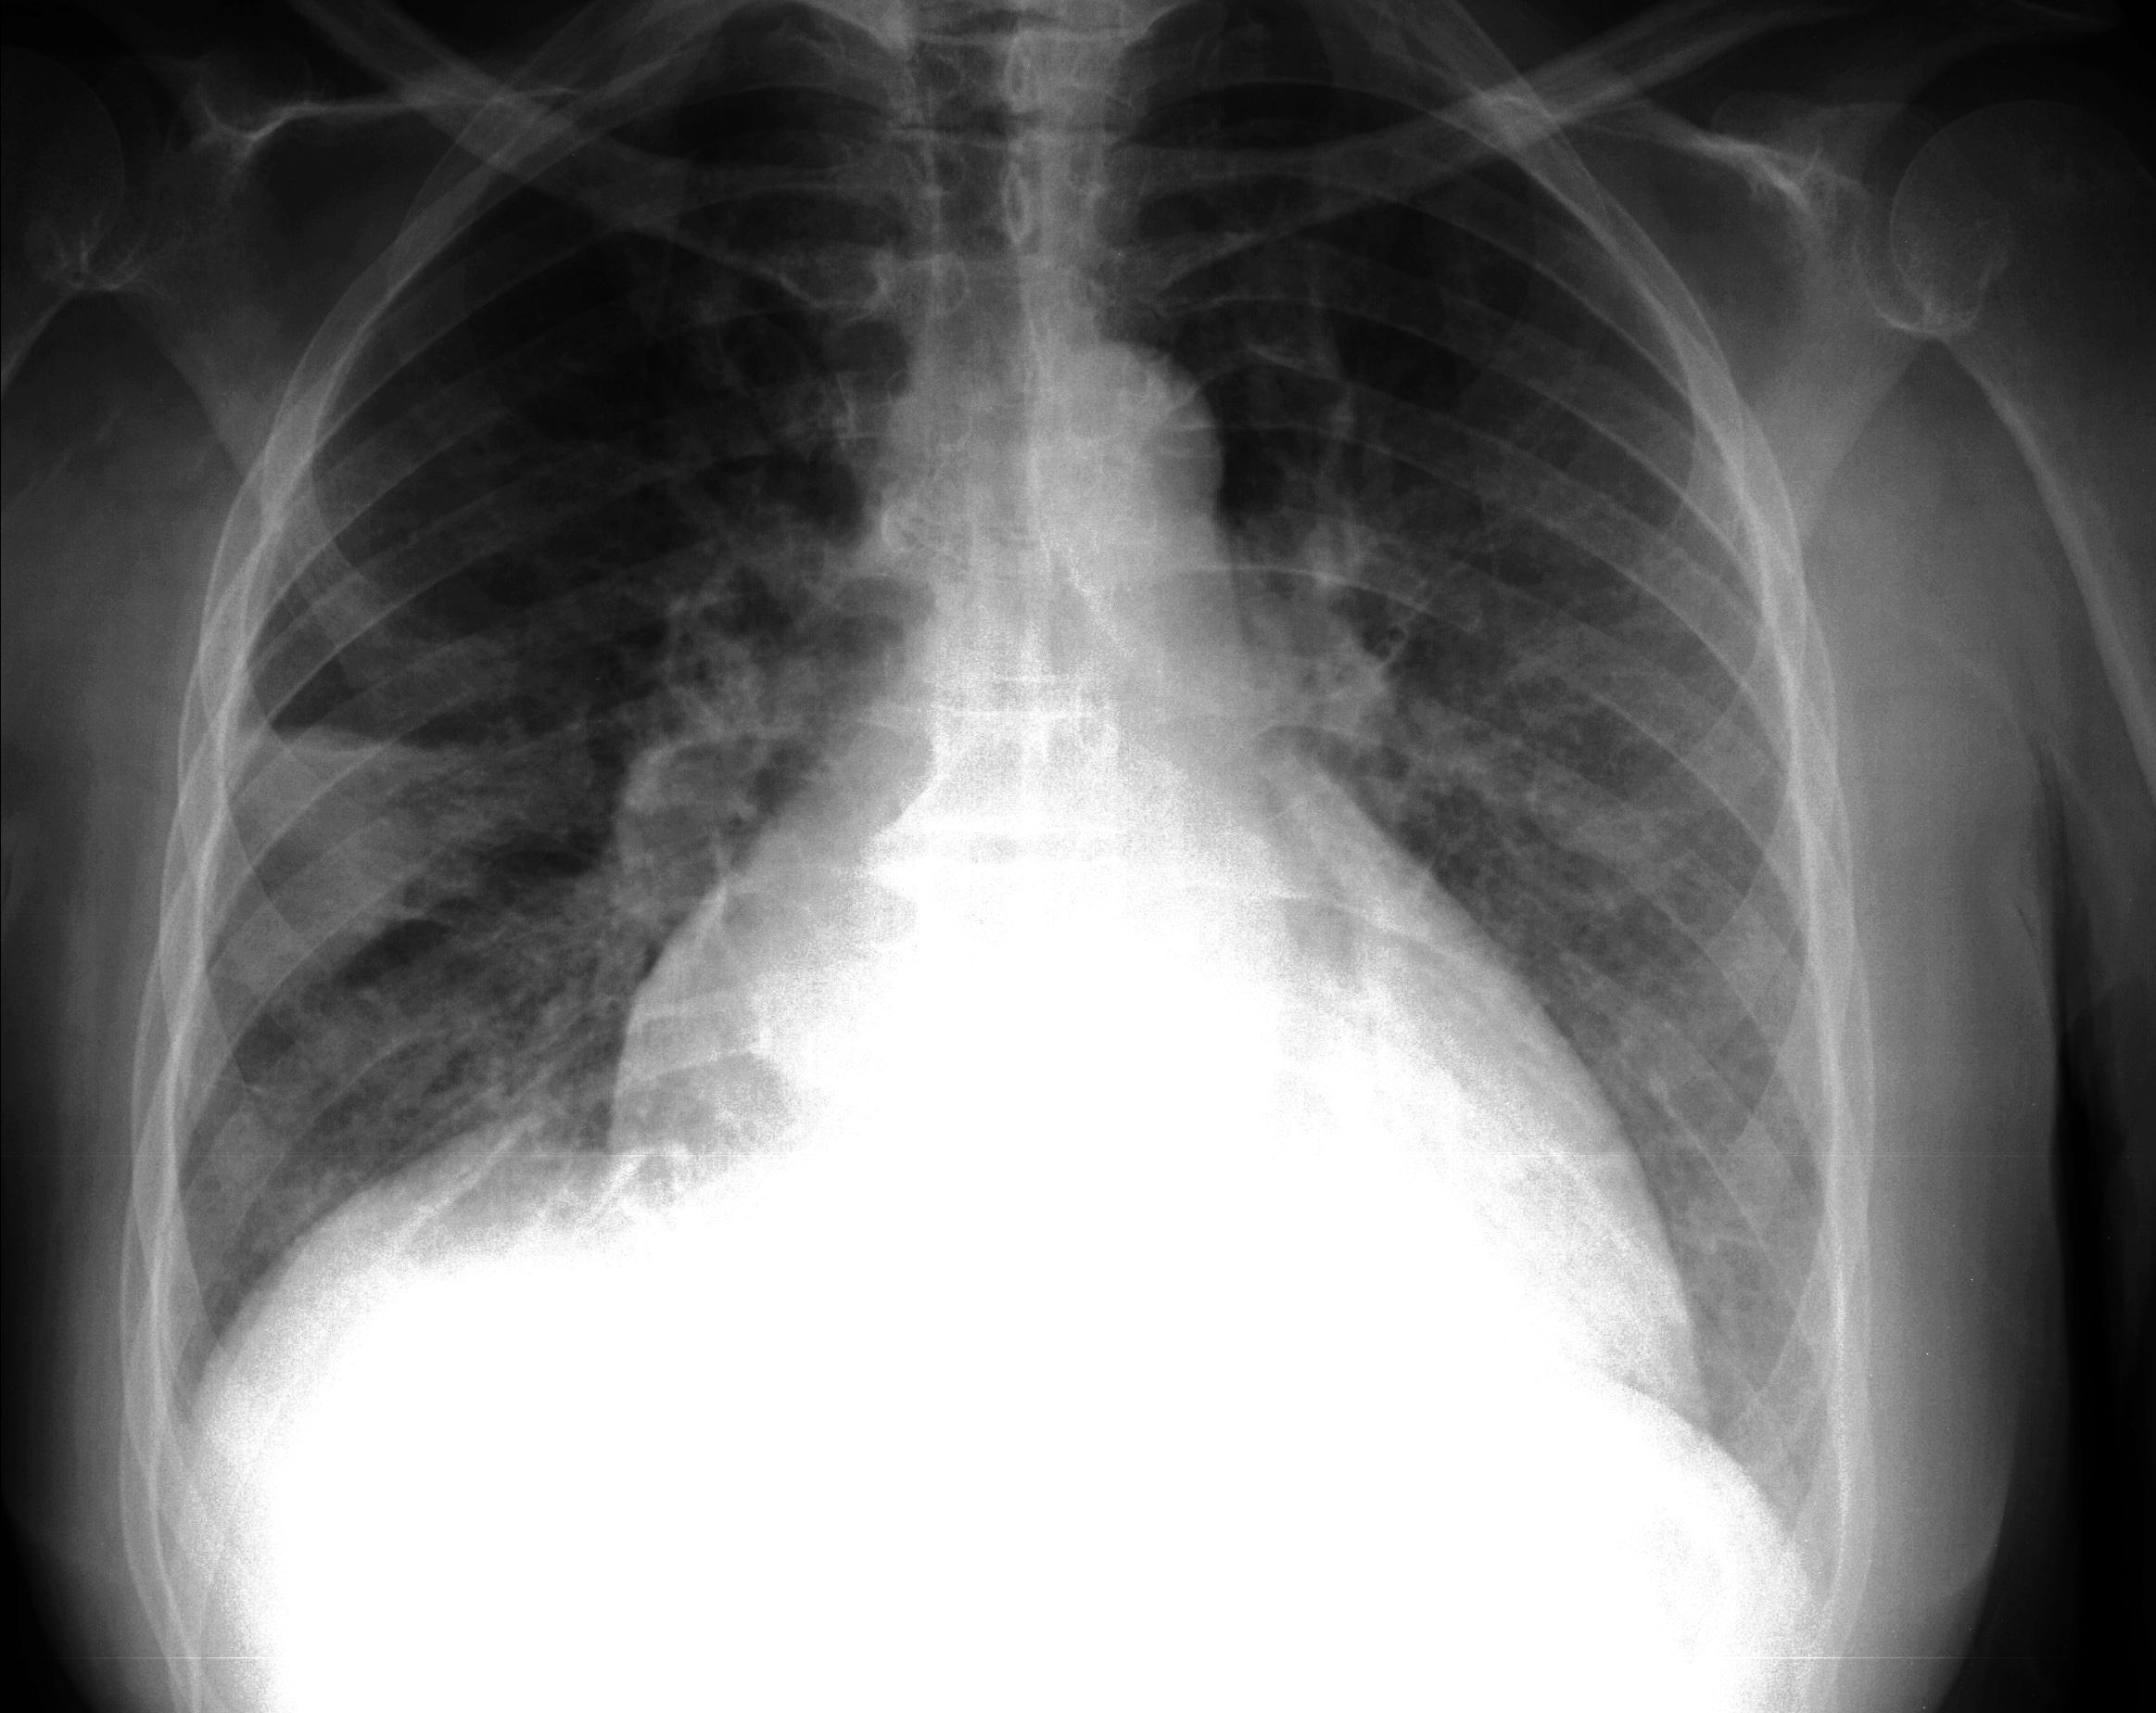

- Рентгенографию. На рентгеновских снимках можно увидеть увеличение границ сердца и корней легких. При альвеолярном отеке в центральных отделах легких наблюдается однородное симметричное затемнение в форме бабочки, а гораздо реже — отдельные очаги.